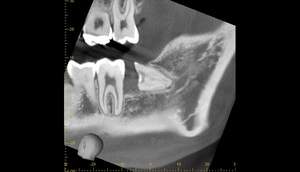

麻布十番歯科での右下の親知らずが真横に生えている症例のレントゲン写真

右下の親知らずが気になると言う主訴でいらっしゃった患者様です。

レントゲンで確認すると、真横にはえており、さらに、下歯槽神経と接触しているようにみえます。

根の形は先細りの形態ですので、抜くのはそこまで難しくないと思われます。根の形の最終確認と、下歯槽神経の位置確認のためにCTを撮影することにしました。

CT画像①

麻布十番歯科での右下の親知らずが真横に生えている症例のCT画像①

CTの1部分の画像です。下歯槽神経と親知らずはほんの少し接触しているような状態でした。リスクなど説明し、2回法で抜いていくことにしました。